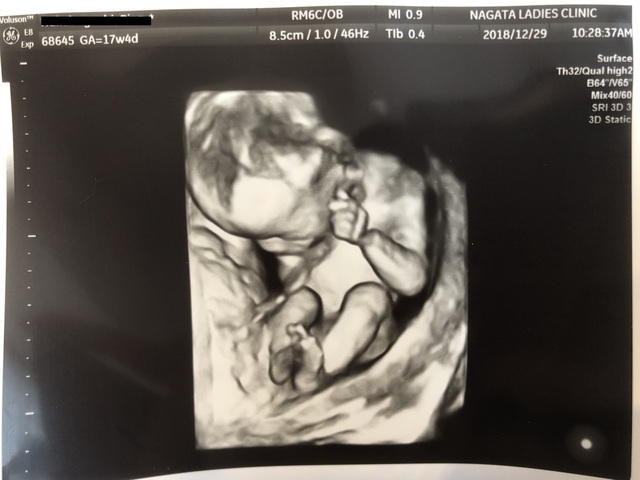

17週4日(17w4d・男の子)|ayu♡ さん(35歳)

エコー写真撮影時のエピソード:

この子の初めての4Dエコーでした。健診が終わって会計待ちの間に、主人にエコーの写メを送りました。

主人は男の子が欲しかったので、ファイティングポーズをしているエコーだったから、男の子に間違いないと!しばらくして主治医からも男の子だろうと言われ、喜んでいた主人を思い出します。